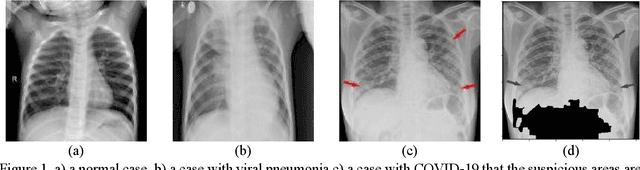

Abstract:As the rapid spread of coronavirus disease (COVID-19) worldwide, chest X-ray radiography has also been used to detect COVID-19 infected pneumonia and assess its severity or monitor its prognosis in the hospitals due to its low cost, low radiation dose, and wide accessibility. However, how to more accurately and efficiently detect COVID-19 infected pneumonia and distinguish it from other community-acquired pneumonia remains a challenge. In order to address this challenge, we in this study develop and test a new computer-aided diagnosis (CAD) scheme. It includes several image pre-processing algorithms to remove diaphragms, normalize image contrast-to-noise ratio, and generate three input images, then links to a transfer learning based convolutional neural network (a VGG16 based CNN model) to classify chest X-ray images into three classes of COVID-19 infected pneumonia, other community-acquired pneumonia and normal (non-pneumonia) cases. To this purpose, a publicly available dataset of 8,474 chest X-ray images is used, which includes 415 confirmed COVID-19 infected pneumonia, 5,179 community-acquired pneumonia, and 2,880 non-pneumonia cases. The dataset is divided into two subsets with 90% and 10% of images in each subset to train and test the CNN-based CAD scheme. The testing results achieve 94.0% of overall accuracy in classifying three classes and 98.6% accuracy in detecting Covid-19 infected cases. Thus, the study demonstrates the feasibility of developing a CAD scheme of chest X-ray images and providing radiologists useful decision-making supporting tools in detecting and diagnosis of COVID-19 infected pneumonia.